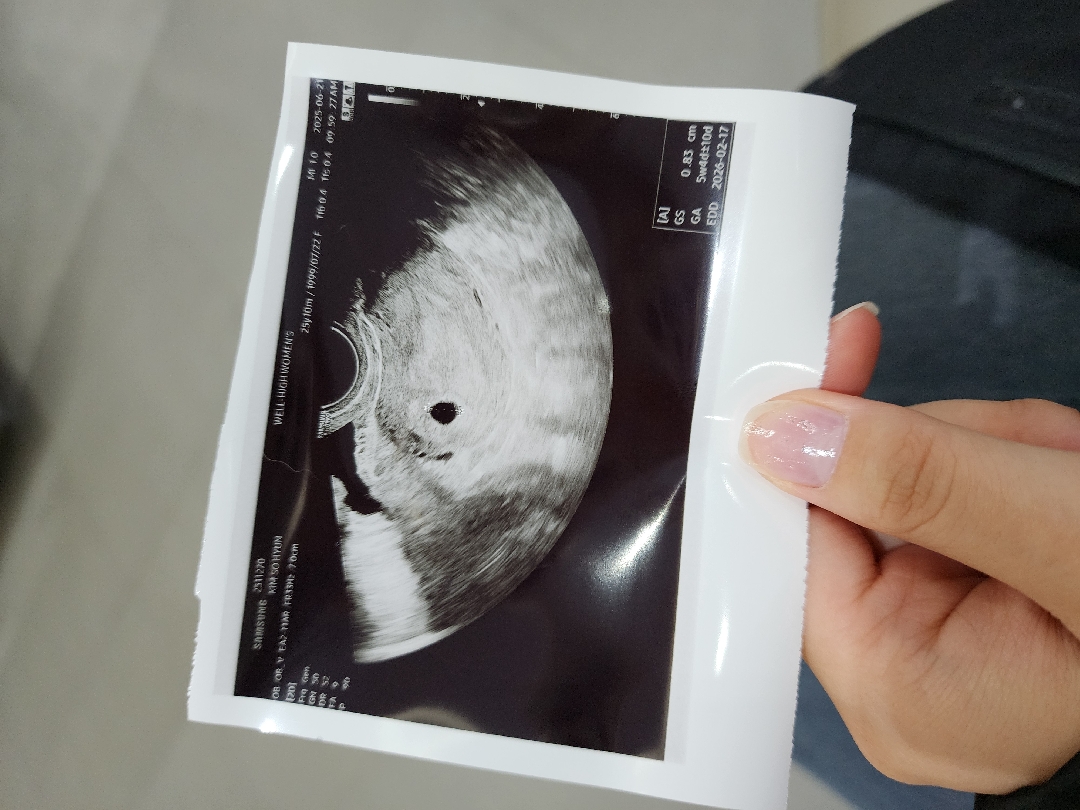

5주 1일차 아기집 보고 왔어요

막생 5월 17일 테스트 확인 6월 13일 피검사 6월 14일 아기집 확인 6월 21일 6월 17일쯤 갈색 냉이 조금씩 보여서 오늘 검사 받으며 말씀 드리니.... 유산초기 증상을 수도 있다고 하셔서 오늘 질 검사랑 이런거 다 하고 왔네요ㅠㅠ 아기집은 잘 자라고 있다고 하시는데... 갈색 냉.... 괜찮겠죠..?